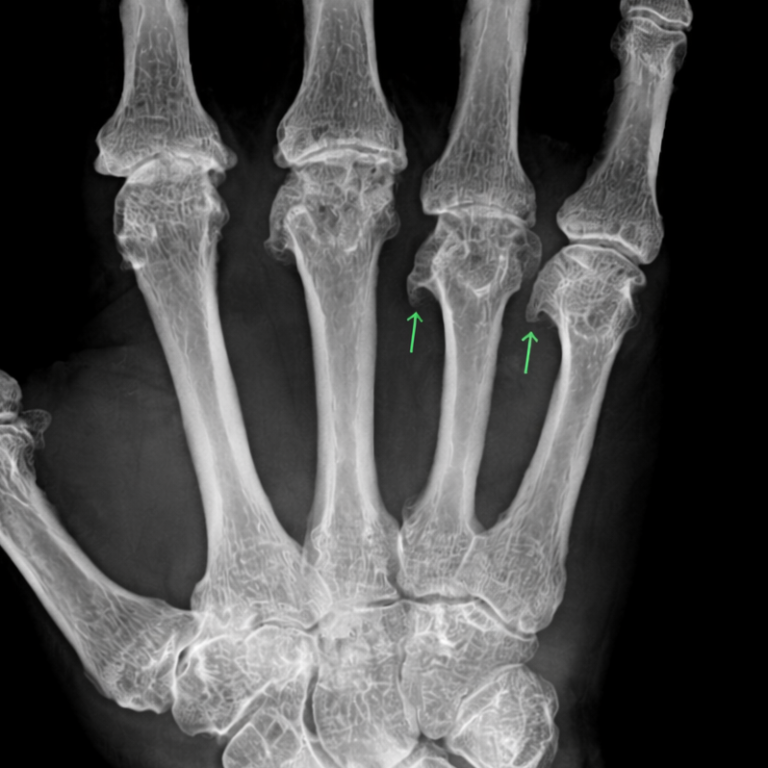

Die rheumatoide Arthritis ist eine chronisch-entzündliche Autoimmunerkrankung, die vor allem die Gelenke betrifft. Typisch sind schmerzhafte Schwellungen, Morgensteifigkeit und eine zunehmende Bewegungseinschränkung. Unbehandelt kann es zu bleibenden Gelenkschäden kommen, selten sind auch innere Organe beteiligt.

Eine frühzeitige Diagnose und eine konsequente, individuell angepasste Therapie sind entscheidend, um die Entzündungsaktivität zu kontrollieren, Beschwerden zu lindern und die Gelenkfunktion langfristig zu erhalten.